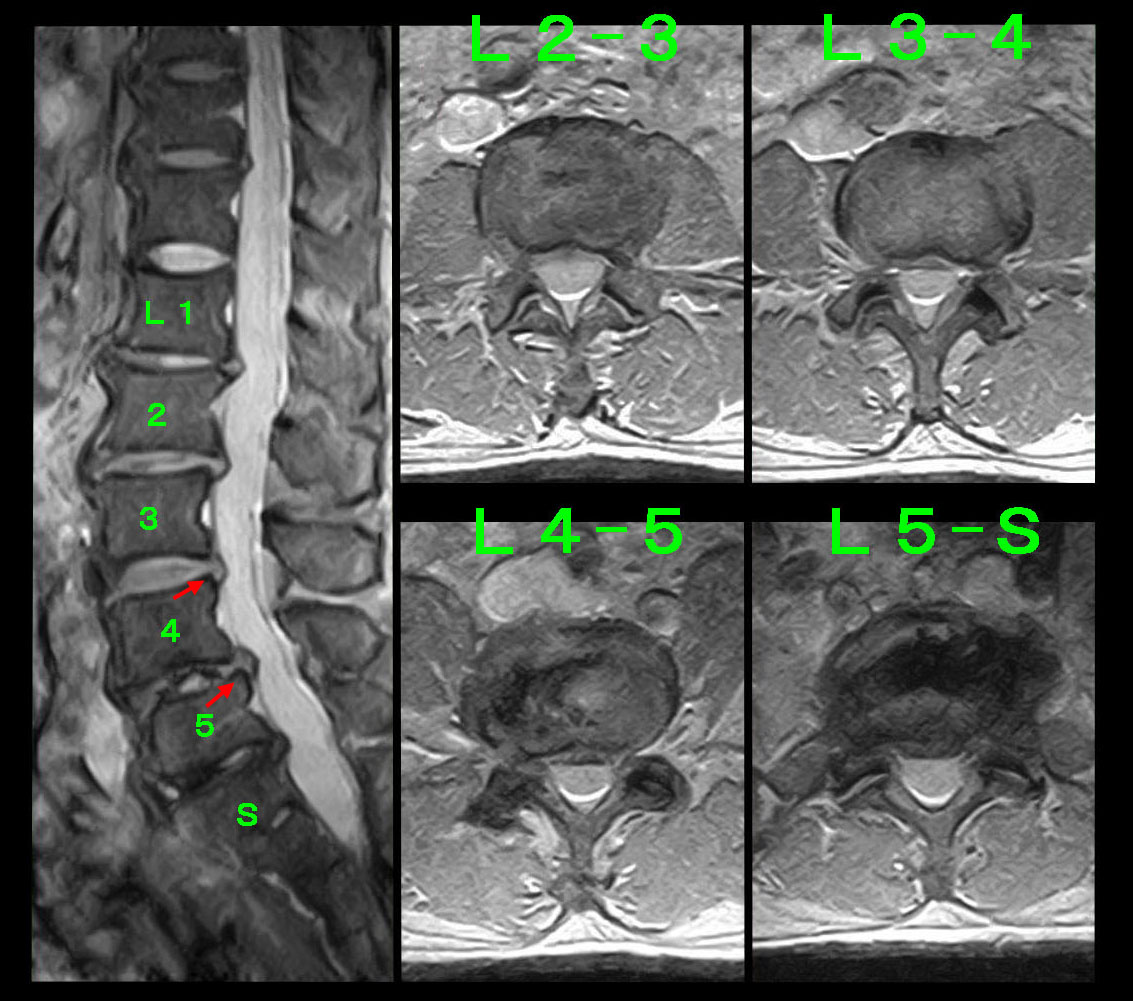

この方の場合、71才の男性よりも腰椎での脊柱管狭窄の所見はL34・L45で重度であり、下垂足を発症しても仕方ないかなという状態です。

平野・MR.jpg